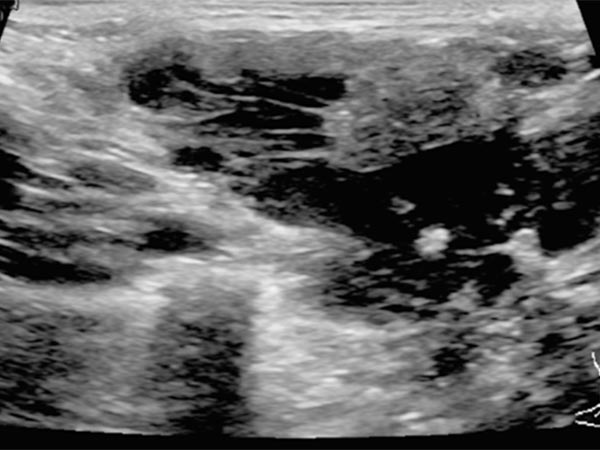

In der B-Bild-Sonographie (Querschnitt) zeigt sich die venöse Malformation ebenfalls kombiniert echoarm bis echofrei. Die echoreicheren Anteile entsprechen Abschnitten der VM, in denen das enthaltene Blut bereits geronnen ist. In den echofreien Anteilen ist das enthaltene Blut noch flüssig. Zudem findet sich ein kleiner Phlebolith in der Läsion, dies ist praktisch pathognomonisch für eine venöse Malformation.